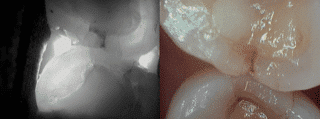

Ces photographies ont été prises avec l’utilisation de la technologie Lum G2. Elles permettent de démontrer son pouvoir dans le diagnostique des caries, des fractures et des fêlures.

Lum Decay Under Sealant - Clinique dentaire Morin-Houle in Hull